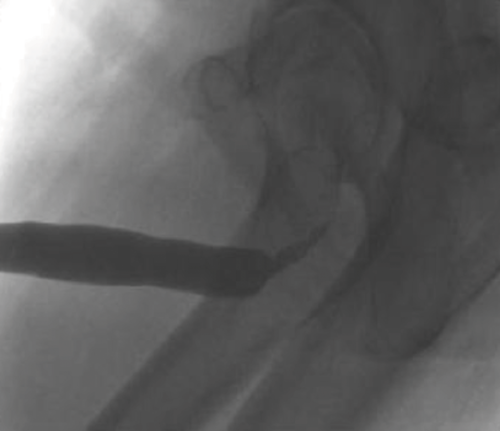

Endoscopic visualisation via cystourethroscopy can identify the location of the stricture but provides minimal information on stricture length. Ultrasonography is useful in demonstrating depth of spongiofibrosis, whilst contrast studies such as retrograde urethrography and voiding cystourethrography accurately demonstrate the anatomical location and length of the stricture, which guides further treatment. An example of a urethrogram can be seen in Figure 2.

Figure 2. Ascending urethrogram demonstrating bulbar urethral stricture.